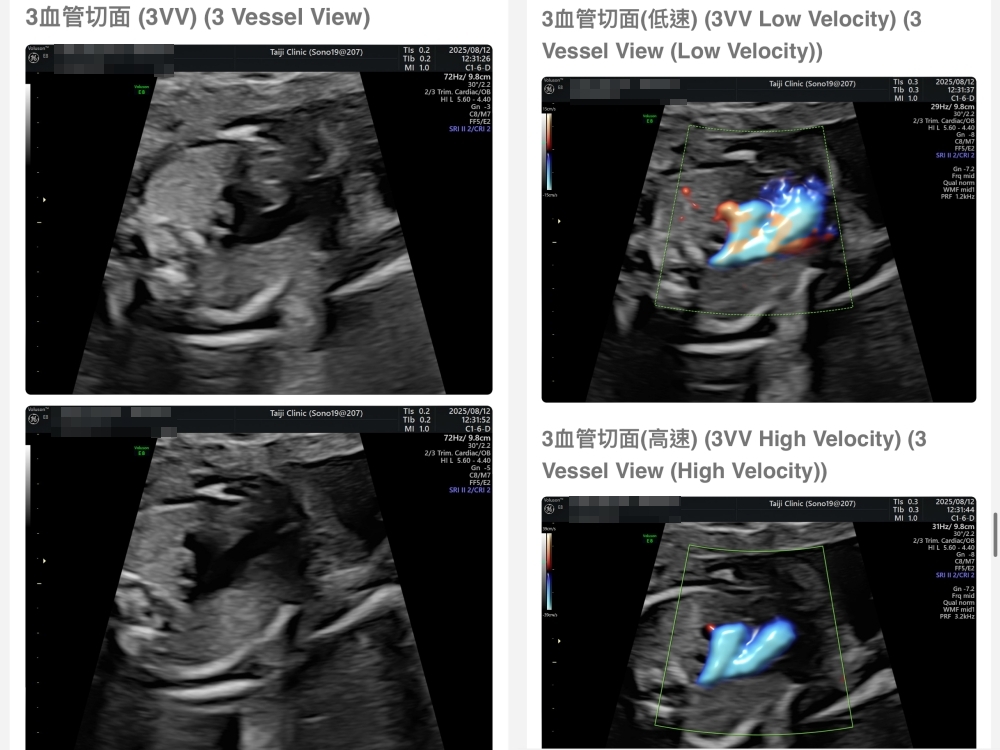

【台兒|高層次超音波|檢查結果】

▲離開診所後會收到MAIL,我們14:05離開,大約是16:45收到mail,裡面會有滿滿的超音波照片,紀錄的很詳細!也會提供紙本的報告,可以給日後產檢的醫師做參考👌